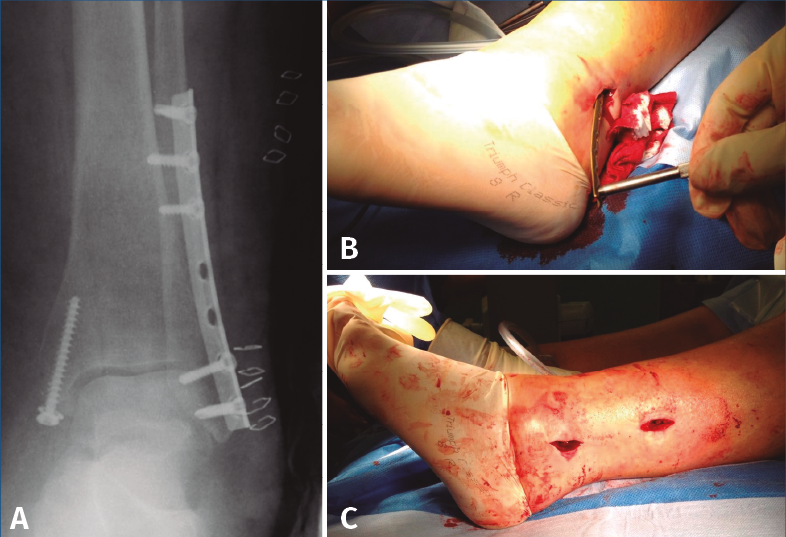

A nivel de partes blandas, las placas bloqueadas con un diseño de bajo perfil y precontorneadas favorecen la contención de fragmentos pequeños y la menor irritación de la piel. Sin embargo, debe tenerse en cuenta el grosor de la placa y si contamos con suficiente piel para la cobertura de esta por posibles complicaciones(29,31). Existe la posibilidad de la colocación percutánea de la placa para una menor agresión de las partes blandas (Figura 3).

Figura 3. A: placa de tercio de caña bloqueada (con tornillos no bloqueados en la zona proximal); B: implante mediante técnica percutánea; C: incisiones finales.